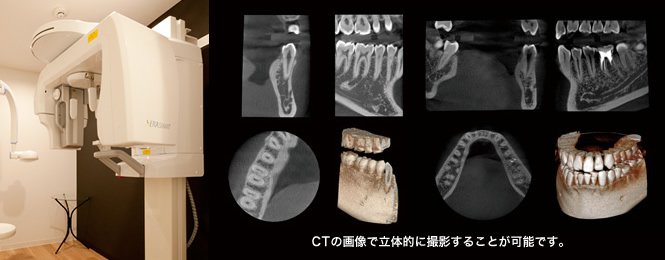

Xガイドは、インプラント手術に置いて最先端技術になり導入している所はまだ少なく、あごの骨のCTを撮影した後、コンピュータ上にて診断、分析、治療のシミュレーションを行い、そのシミュレーション通りに手術が行われるよう、ナビゲーションしてくれるシステムです。

GPS測定によるナビゲーションシステムを用いて、インプラントを間違いなく最適な位置、角度に埋入することができ誤差は0.2mm以内と報告されております。また、このシステムを使うことにより、骨の中の神経や血管の走行などをリアルタイムで立体的に確認しながら手術を行えるため、手術中のトラブル回避へとつながり安心安全手術を行っていきます。

まずはインプラント治療で一番大事な診査、診断を行います

ここでCT撮影、口腔内写真、模型などを使い手術のシミュレーションを行います。